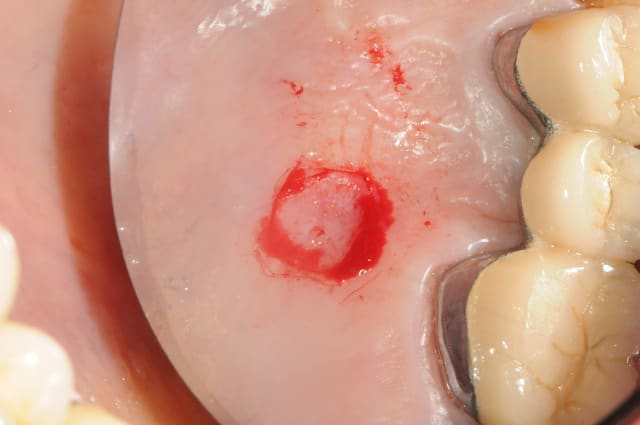

-22:dent foutue

-avulsion au périotome' un p'tit coup à gauche, un ptit coup à droite...)

- la dent avec du beurk au bout

-le site d'extraction

-vérification de l'existence d'une table externe

-implantation (je passe les détails)

- prélèvement d'une petite pièce de gencive libre

- suture de la "pastille" de gencive

-j+10 jours

-+1 mois